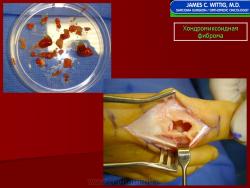

Рентгенологическое исследование показывает, что опухоль растет экзофитно в зоне метафиза и распространяется по направлению к эпифизу. Она имеет четкие и фестончатые очертания. На фоне характерных литических изменений изредка видны участки обызвествления. Наиболее агрессивный вид имеет хондромиксоидная фиброма, локализующаяся в позвонках. Здесь часто отмечается прорастание надкостницы. Макроскопически представляет собой четко отграниченную опухоль, имеющую дольчатое строение, плотную консистенцию, серовато-белый или синюшно-серый цвет. При прорастании новообразования через кортикальный слой надкостница сохраняется. В редких случаях наблюдается имплантация опухолевой ткани в окружающие мягкие ткани. Для лечения хондромиксоидной фибромы используется кюретаж. Рецидивы наблюдаются в 10—15 % случаев, обычно в течение первых 2 лет после операции, чаще всего у лиц моложе 15 лет.

Макроскопическая картина. Опухолевая ткань при хондромиксоидной фиброме имеет характерный вид несколько выбухающей из границ белесовато-голубой ткани.

Рентгенологическое исследование показывает, что опухоль растет экзофитно в зоне метафиза и распространяется по направлению к эпифизу. Она имеет четкие и фестончатые очертания. На фоне характерных литических изменений изредка видны участки обызвествления. Наиболее агрессивный вид имеет хондромиксоидная фиброма, локализующаяся в позвонках. Здесь часто отмечается прорастание надкостницы. Макроскопически представляет собой четко отграниченную опухоль, имеющую дольчатое строение, плотную консистенцию, серовато-белый или синюшно-серый цвет. При прорастании новообразования через кортикальный слой надкостница сохраняется. В редких случаях наблюдается имплантация опухолевой ткани в окружающие мягкие ткани. Для лечения хондромиксоидной фибромы используется кюретаж. Рецидивы наблюдаются в 10—15 % случаев, обычно в течение первых 2 лет после операции, чаще всего у лиц моложе 15 лет.